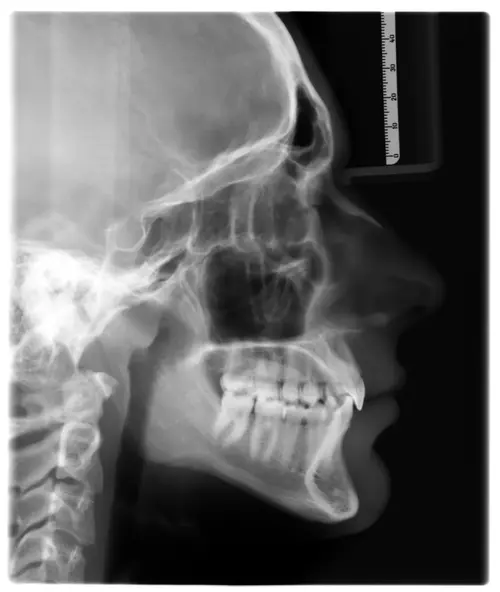

I’m 15.5 with noticeable jaw asymmetry - right ramus is longer than left and a slightly recessed lower jaw. My orthodontist said the it is skeletal and IF i want to correct it i may need jaw surgery (probably a bsso + genio) , but I haven’t been to a maxillofacial surgeon yet since i am 15 and my ortho said that there is no reason to go since they my jaw will still grow.

Even though it doesnt look that bad in xrays in my opinion the assymetry is noticeable and bsso would benefit me, becouse of my pretty short ramus (atleast it apears so on my left side) and mandible reccession